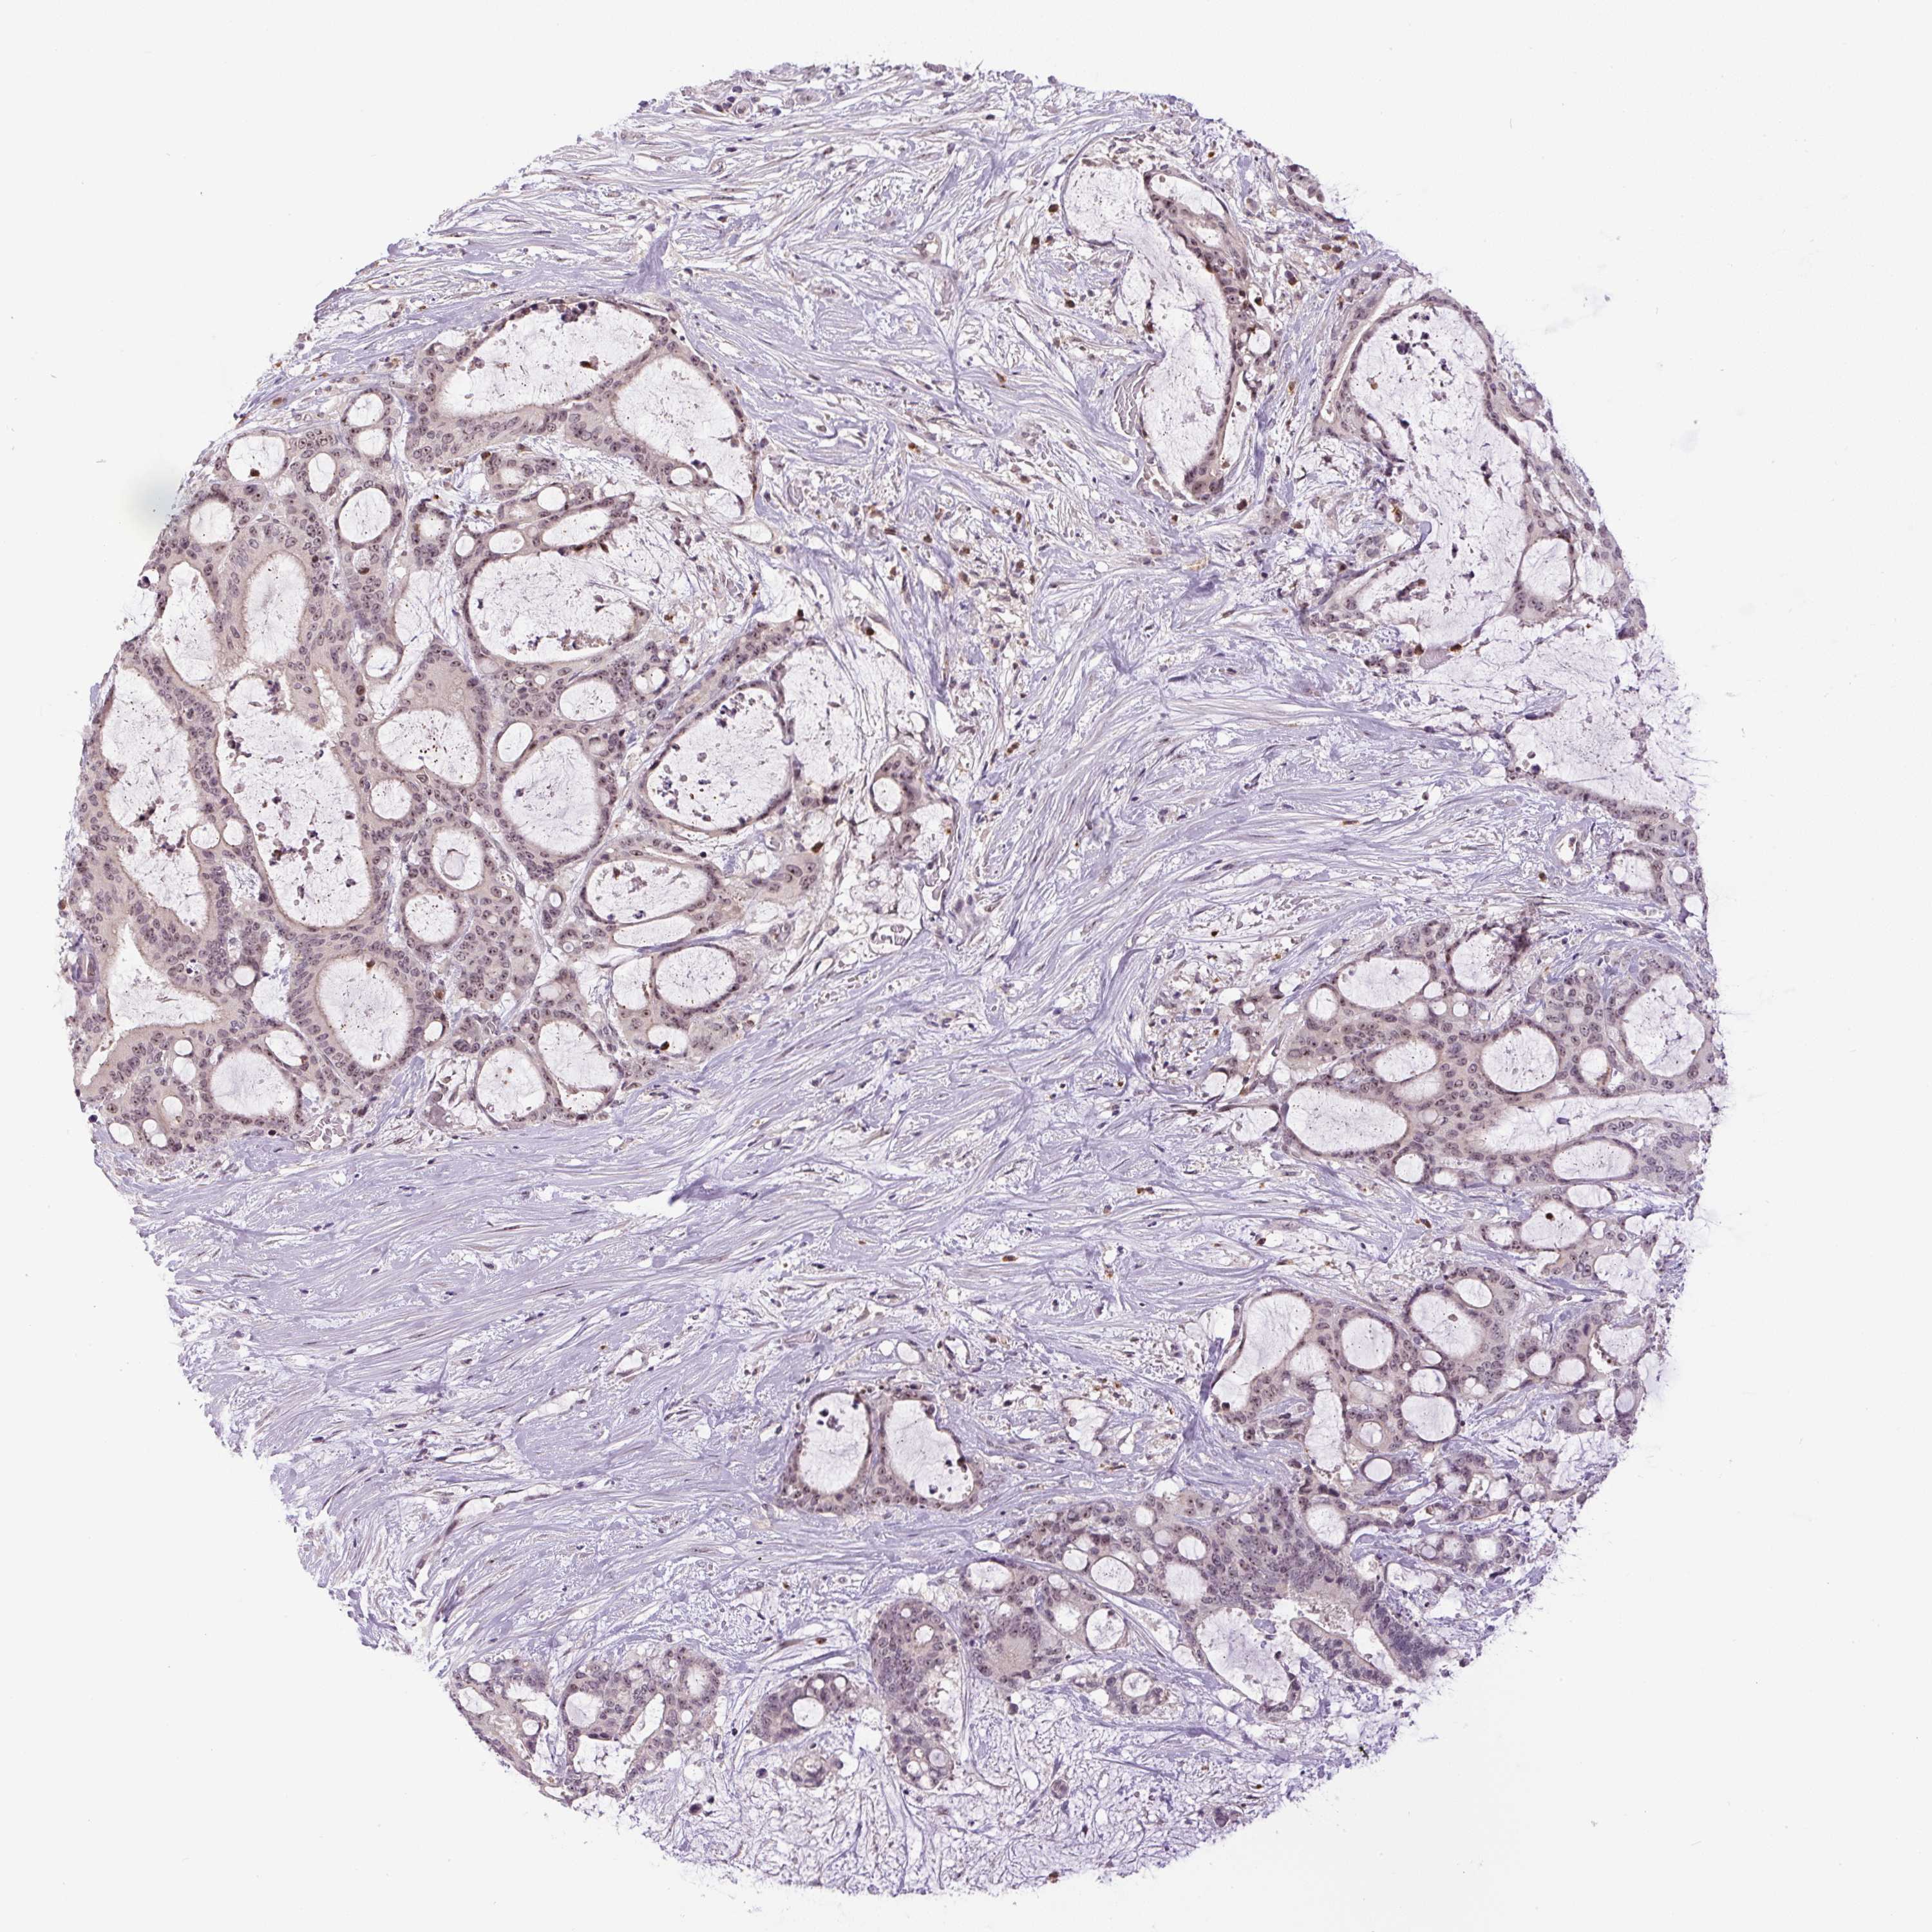

LIVER CANCER - Protein expressioni

A mouse-over function shows sample information and annotation data. Click on an image to view it in a full screen mode. Samples can be filtered based on level of antibody staining by selecting one or several of the following categories: high, medium, low and not detected. The assay and annotation is described here.

Note that samples used for immunohistochemistry by the Human Protein Atlas do not correspond to samples in the TCGA dataset.

Antibody stainingi

Antibody staining in the annotated cell types in the current human tissue is reported as not detected, low, medium, or high, based on conventional immunohistochemistry profiling in selected tissues. This score is based on the combination of the staining intensity and fraction of stained cells.

Each image is clickable and will lead to virtual microscopy that enables deeper exploration of all samples and also displays staining intensity scores, fraction scores and subcellular localization as well as patient and tissue information for each sample.

Antibody HPA052590

Antibody HPA053608

Staining

High

Cholangiocarcinoma

Carcinoma, Hepatocellular, NOS